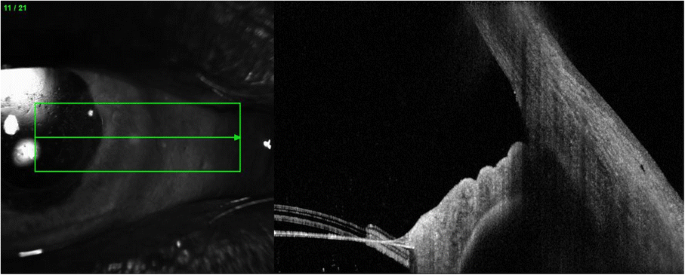

Six weeks post operatively the patient had a wide-open angle with a central IOL and a flat retina (Figs. 5 and 6). Intraocular Pressure without IOP lowering treatment was recorded at 20 mmHg with VA 6/24. He was restarted on IOP lowering topical treatment (G Brinzolamide/Timolol BD).